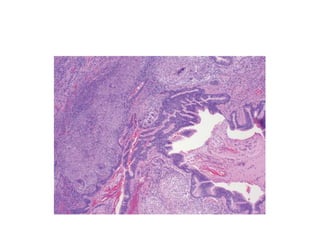

Morphology

• Pleural surface grossly cobblestoned owing to

retraction of scars along the interlobular septa

• Microscopically the hallmark UIP is patchy

interstitial fibrosis & the earliest

manifestation is fibroblastic foci

Ctd…

• Honey comb fibrosis dense, causes collapse of

alveolar walls & formation of cystic spaces

lined by hyperplastic type II pneumocytes or

bronchial epithelium.

• Infiltration of lymphocytes

• Foci of squamous metaplasia & smooth

muscle hyperplasia

• Secondary pulmonary HTn due to intimal

fibrosis & medial thickening of the pulmonary

arteries